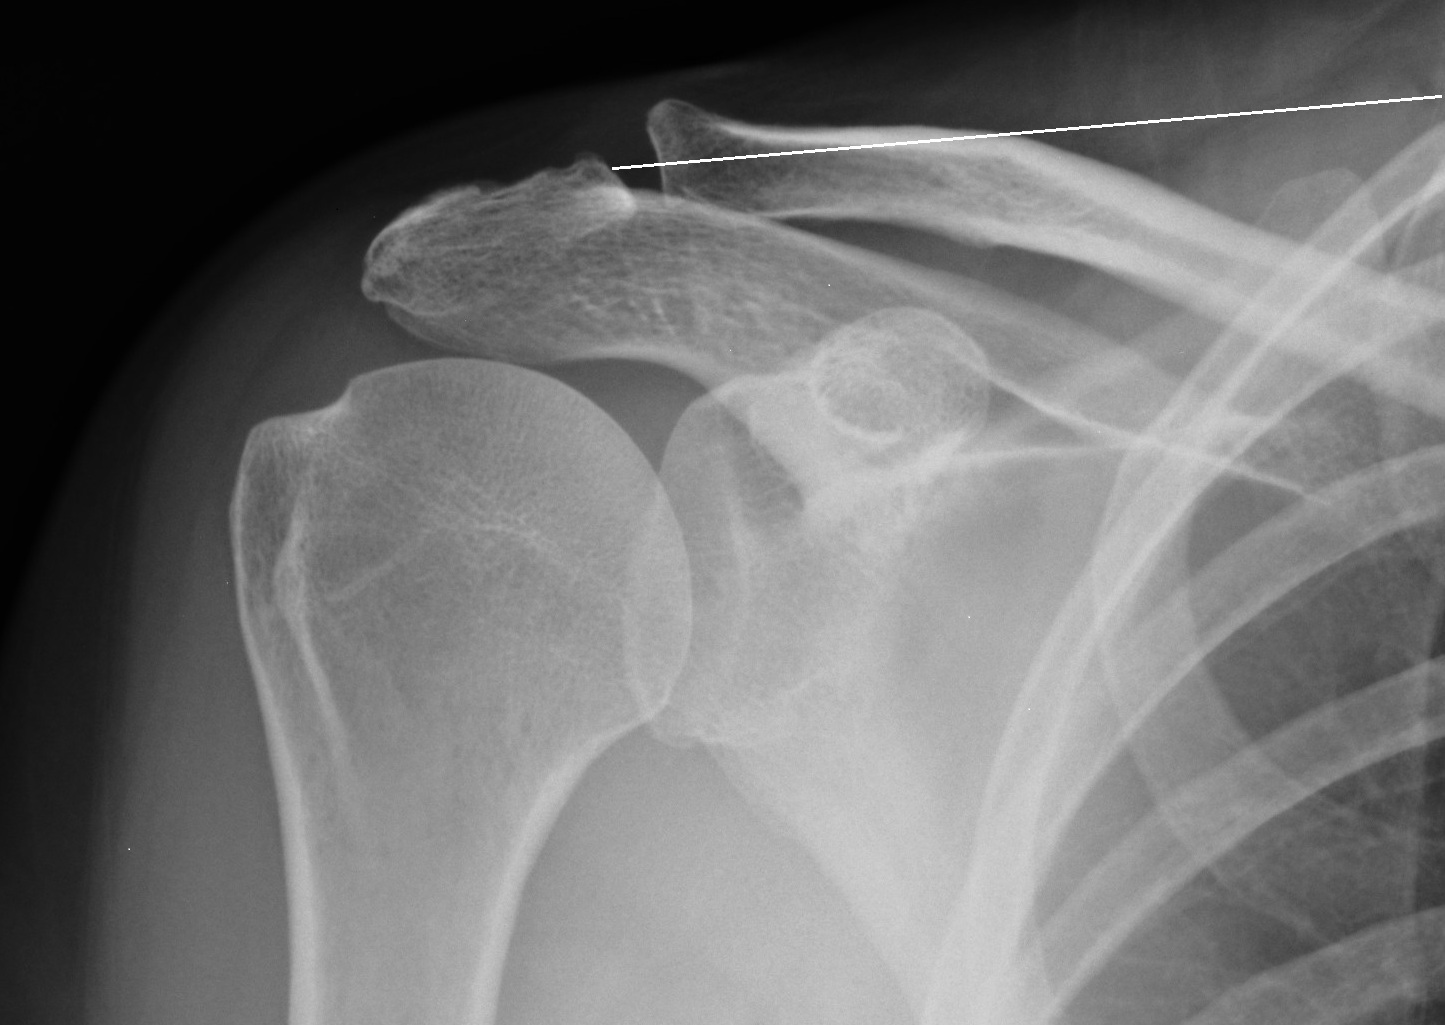

Acromioclavicular joint thesis image This picture shows acromioclavicular joint thesis.

A very significant amount of djd was present in the acromioclavicular joint as compared to the sternoclavicular joint. Their support is real people, and they are always format thesis paper friendly and format thesis paper supportive. Moreover, in order to preserve abduction and rotating capacity, it is mandatory to main. 5th edition, quran is a complete code of life essay in urd. Axial rotation of the clavicula is estimated by minimizing rotations in the acromioclavicular joint.